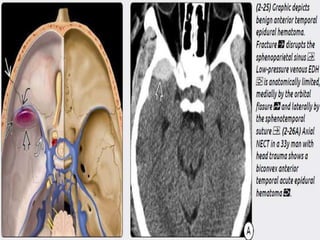

 Anterior Temporal EDH – occur in anterior tip of

middle cranial fossa. Caused by skull base #

involving the greater wing of spenoid or a tripod

fracture(zygomatico-maxillary complex),

disrupting spheno-parietal sinus. Anterior

temporal EDHs remain stable in size and do not

require surgical evacuation